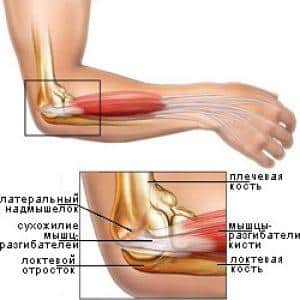

Артрит – это заболевание, связанное с патологическими изменениями в хрящевой ткани, которое вызывает интенсивные болевые ощущения. Для артрита характерно постепенное развитие и хроническое течение. Локтевые суставы подвержены воспалительным процессам не реже, чем другие суставы, особенно в результате различных травм. Если такие травмы происходят регулярно, риск развития артрита значительно возрастает.

Многие люди часто путают артрит с артрозом, однако в медицинской практике встречаются случаи, когда заболевание сочетает в себе признаки обоих состояний. Артрозо-артрит локтевого сустава проявляется разрушением хрящей и суставов, сопровождающимся выраженным воспалением.

Обычно после падения или удара человек начинает испытывать дискомфорт и боль, а подвижность конечности ограничивается. Особенность локтевого артрита заключается в том, что он может быстро распространяться на другие суставы, приводя к полиартриту. Эта патология чаще всего встречается у пожилых людей. Хотя развитие заболевания происходит медленно, со временем оно может усугубляться и осложняться другими недугами, такими как бурсит или флегмона.